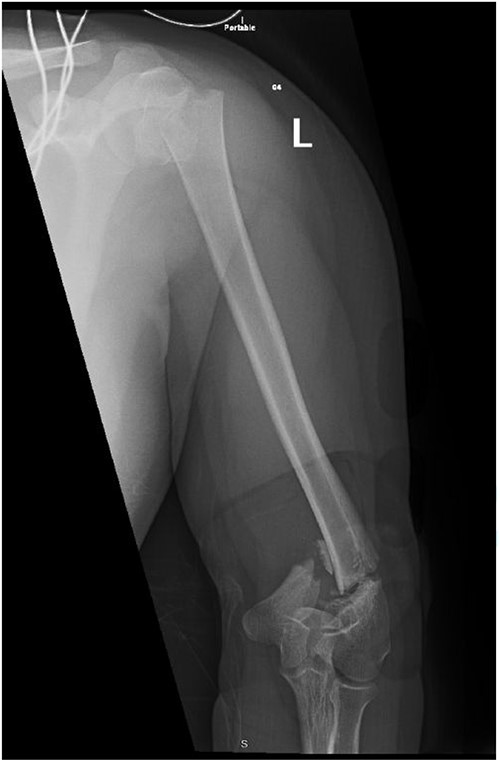

A 14-year-old boy with unknown medical and surgical history was brought by the emergency medical services to the emergency department as a case of multiple trauma after a MVA. Upon arrival, primary and secondary surveys were conducted, and management followed accordingly. After stabilization, all related specialties were involved in case management. Multiple fractures were detected, including left mandible, acetabular, open femur, and humerus fractures, as well as a comminuted pelvic fracture. The humerus fractures involved the proximal and distal area, as shown in Fig. 1.

Anteroposterior (AP) view of the left humerus and elbow pre-operative.